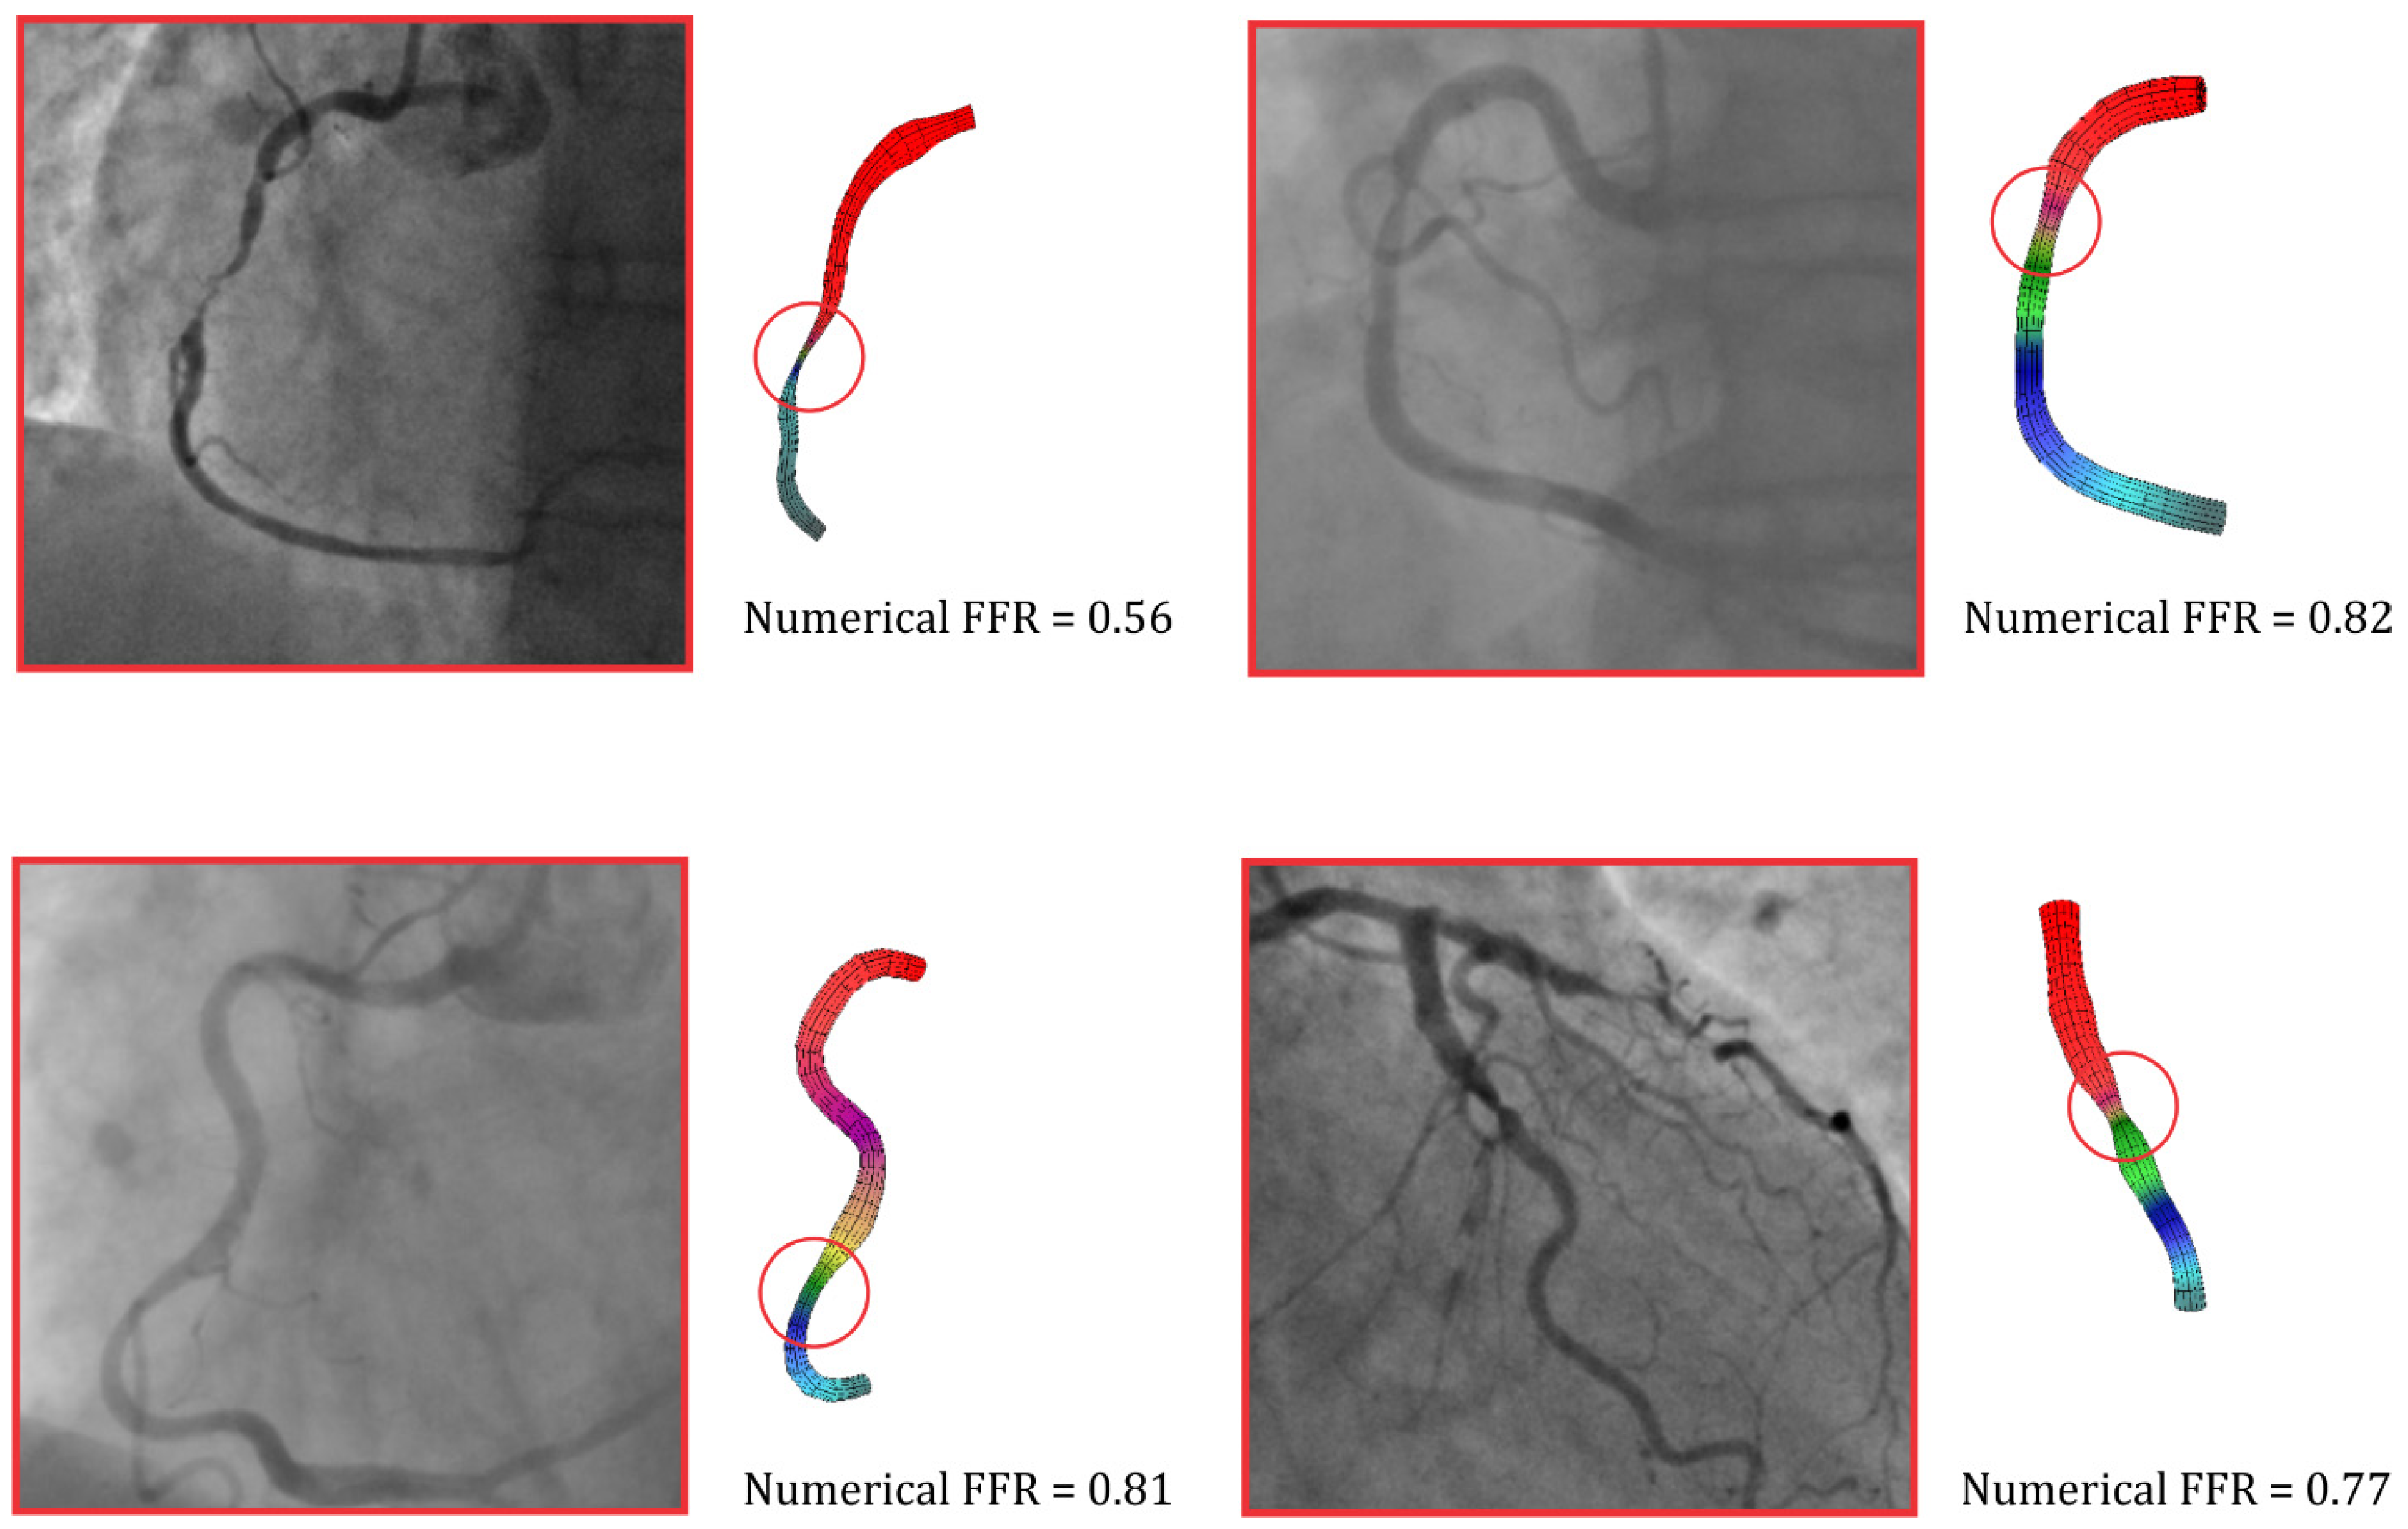

3.3. Numerical Simulation Results

Figure 2 shows the results of four patients after a numerical simulation in the case of a flow rate of 3 mL/s. This flow rate was a standard maximum flow for the measurement of FFR when adenosine was intravenously administrated. A red circle can be seen in Figure 2, which marks the observed stenosis on the artery. As already mentioned, a good agreement between the numerical simulations and the measurements of FFR was obtained, and this was the reason we used numerical results to validate the ML model [25,26].

Figure 2.

Pressure distribution, based on finite element analysis, in the coronary arteries. The FFR value was calculated based on numerical simulations.